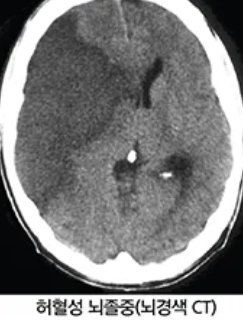

1) 전산화단층촬영(CT 스캔)

뇌의 구조와 혈액 순환이 어떻게 이루어지는지를 확인하기 위해 사용됩니다. CT 스캔은 X선을 사용하여 뇌의 단면 이미지를 생성합니다.